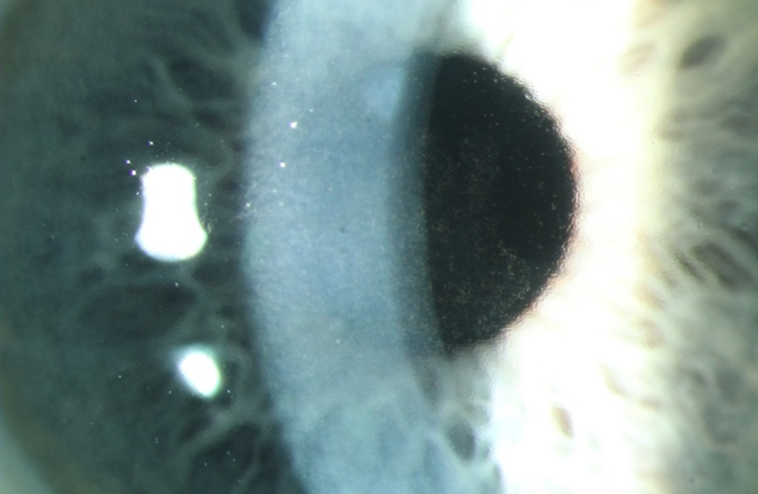

Case: Complaints after cataract surgery

A 68-year-old female underwent cataract surgery at a local hospital four weeks ago. She attended your practice with a complaint of improved but still blurry vision. The preoperative visual acuity on the operated right eye was 0.16 (6/36), and at your examination, it was 0.4 (6/15). The left eye has a mild cataract and a visual acuity of 0.6 (6/10). The intraocular pressures were within normal limits. Both eyes were quiescent with no signs of intraocular inflammation or endophthalmitis. The cornea in both eyes was not fully transparent. The patient mentioned that her mother had very poor vision after cataract surgery on both eyes approximately 20 years ago and needed to use many eye drops at that time.